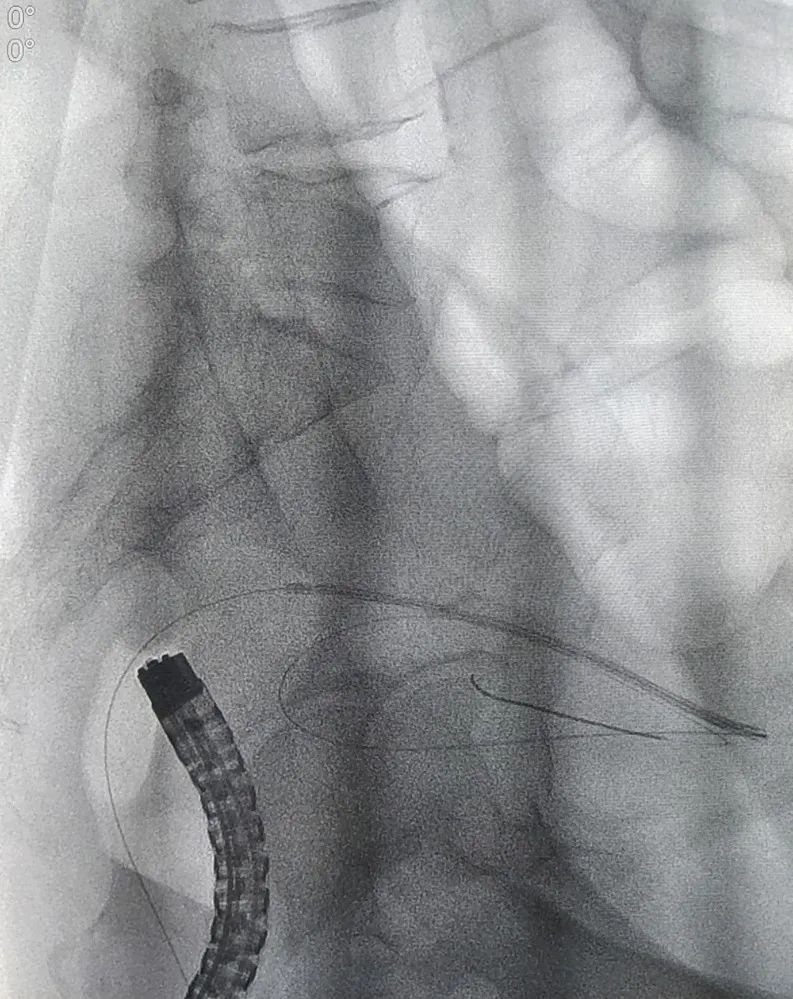

确定诊疗方案后,因患者病情发展较快,消化内科团队为患者开展了急诊肠镜。肠镜检查发现,进镜至距肛缘约10cm处可见一肿物,呈隆起性生长,表面有出血,附有脓苔,考虑直肠恶性肿瘤可能性大,因肠腔水肿、狭窄明显,镜身不能通过,切开刀带导丝进入远端肠道,造影可见肠道呈截断性狭窄。

为快速缓解症状、解除患者疼痛,消化内科郭锐主任及张磊护师结合患者具体情况,决定给予肠道支架置入解除肠道梗阻,使患者免遭肠造瘘的痛苦,为择期手术切除直肠病变做好准备。由于病变导致肠腔严重狭窄,肠道支架置入难度也随之增加,郭锐主任凭借夯实的理论基础及高超的操作技术,通过DSA及肠镜联合引导,成功完成了肠道内金属支架置入术。术后患者恢复良好,能自主排便,腹痛、腹胀症状明显缓解,现已出院。(张 喆)